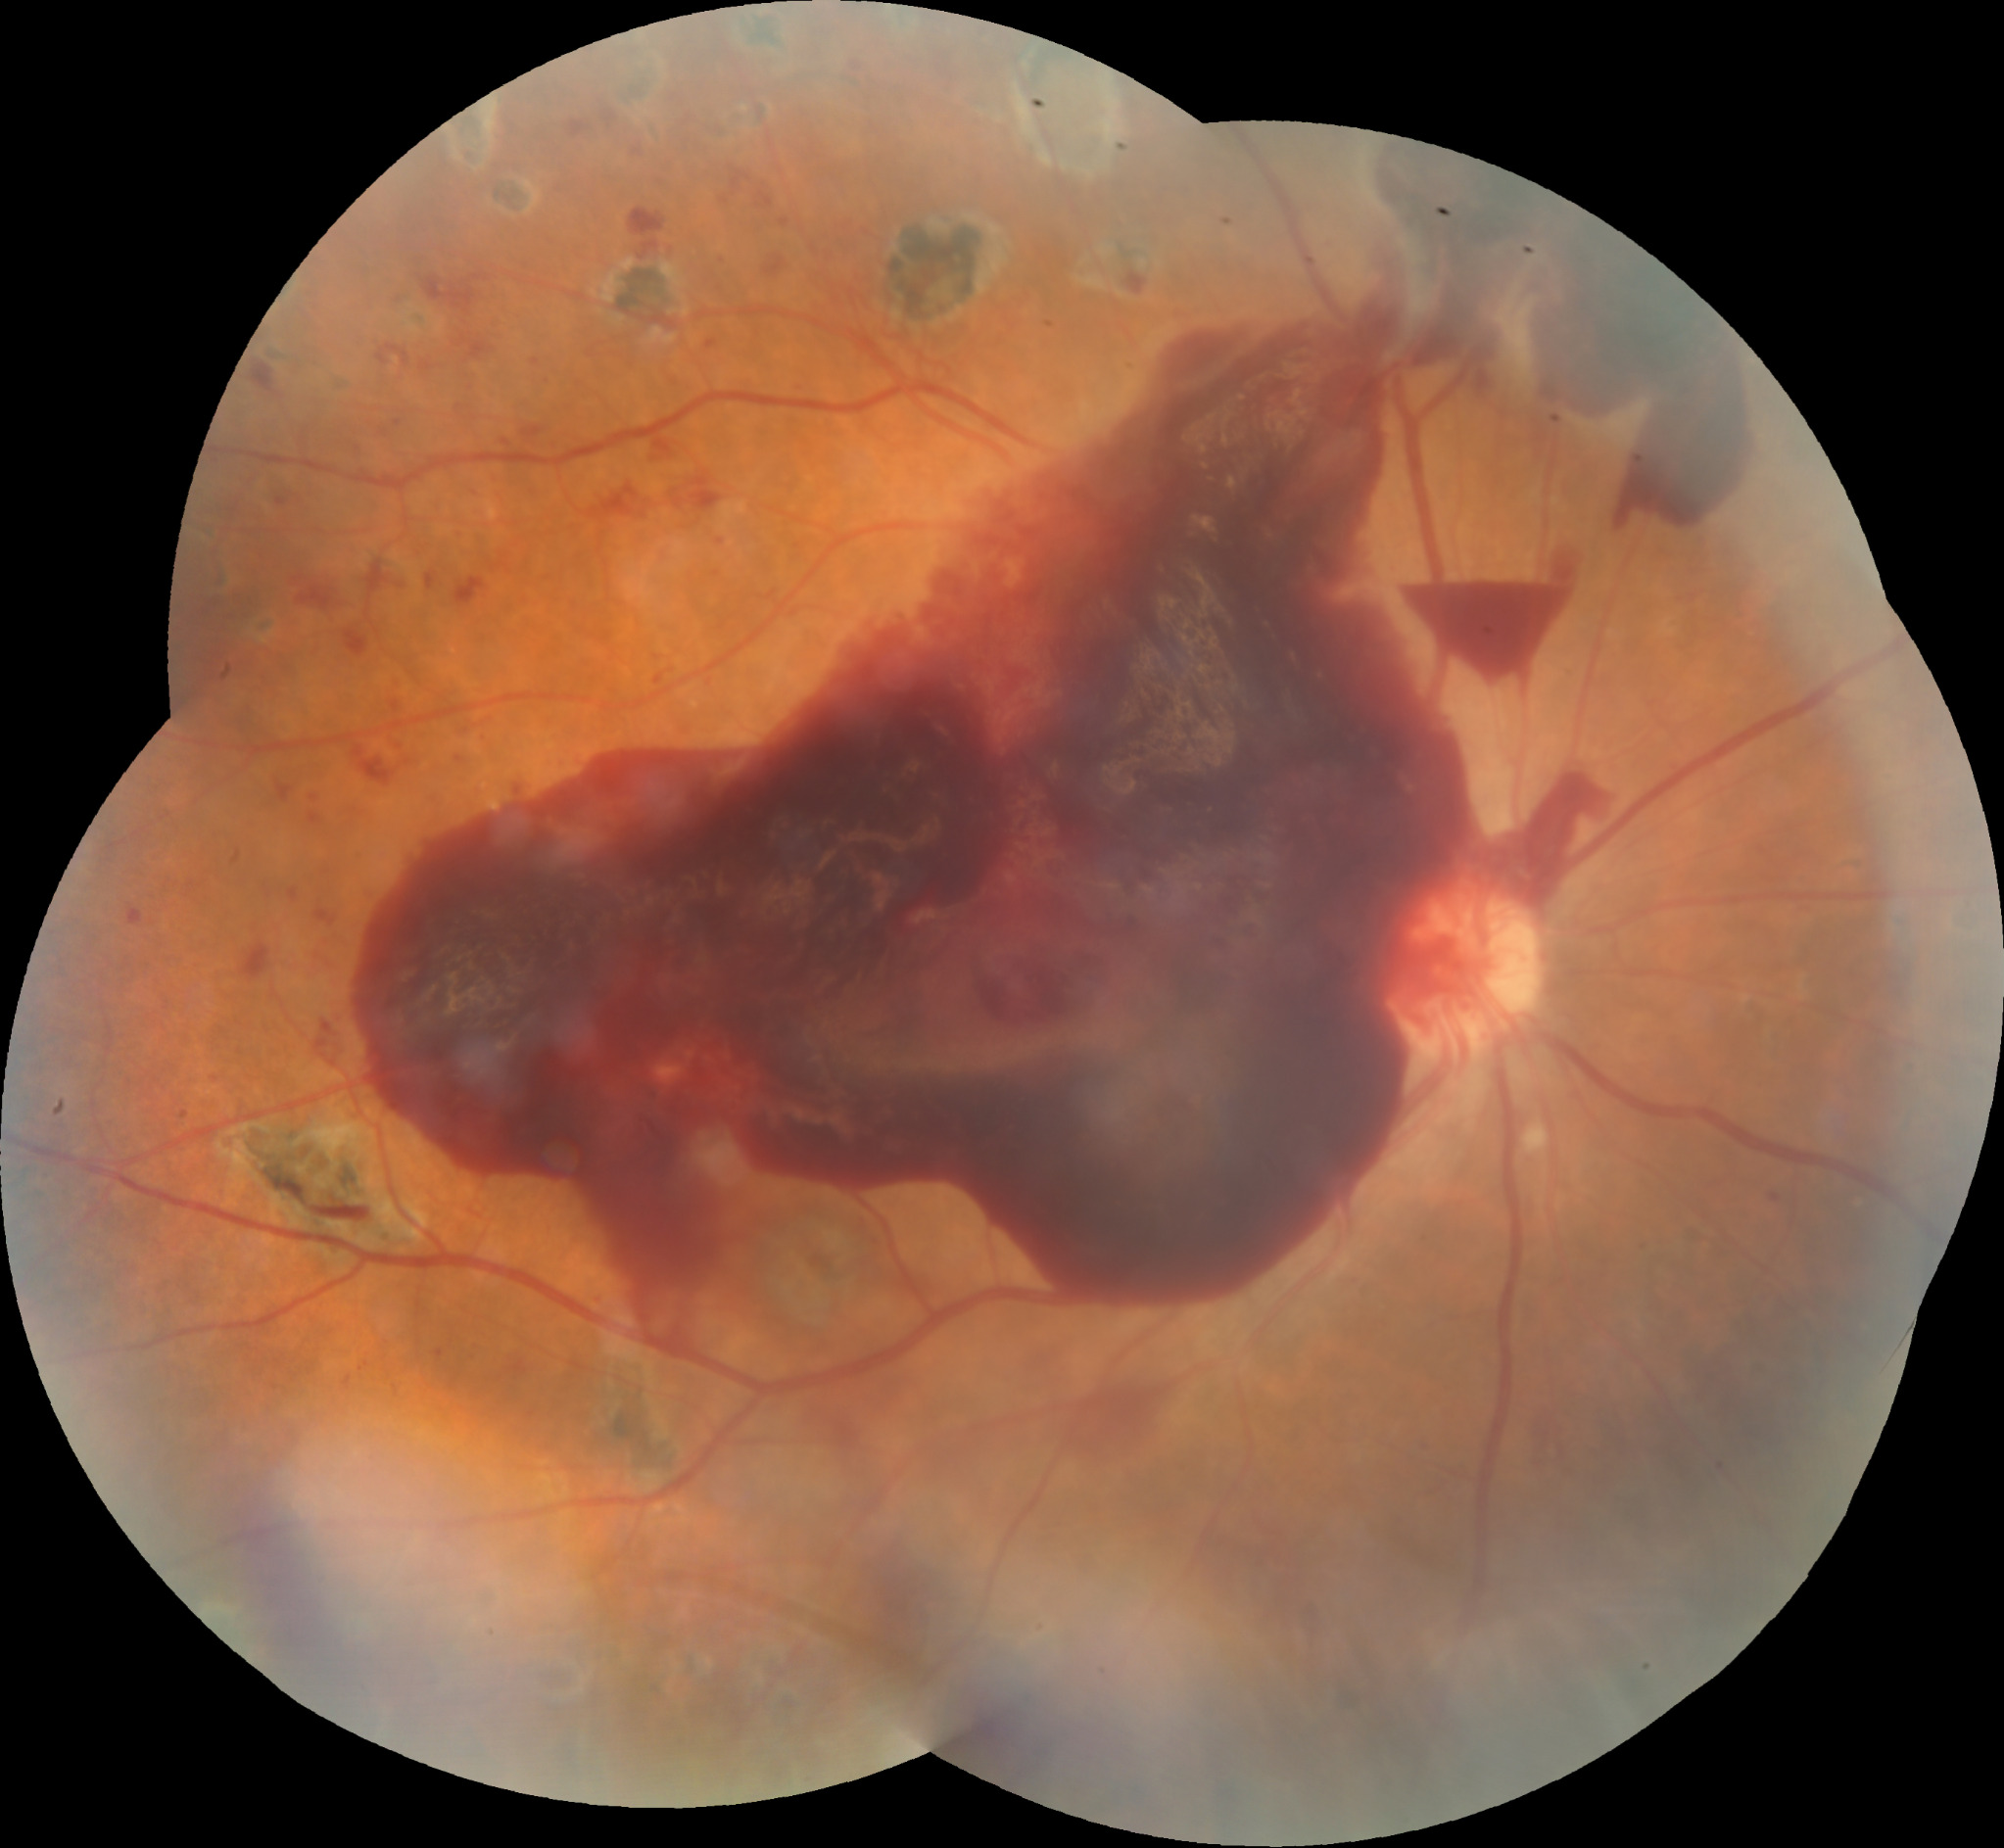

| RDP HV o HS | ![]() ![]() ![]() | ![]() ![]() ![]() | Normal o EMD | Normal o engrosamiento coroideo | ![]() | CIRUGIA: Vitrectomía + Endolaser | H Vítrea H Subhialoidea |

| RDP DRT | ![]() | ![]() | ![]() | ![]() | CIRUGIA: Vitrectomía + Endolaser + Silicón | Tracción sobre todo macular | |